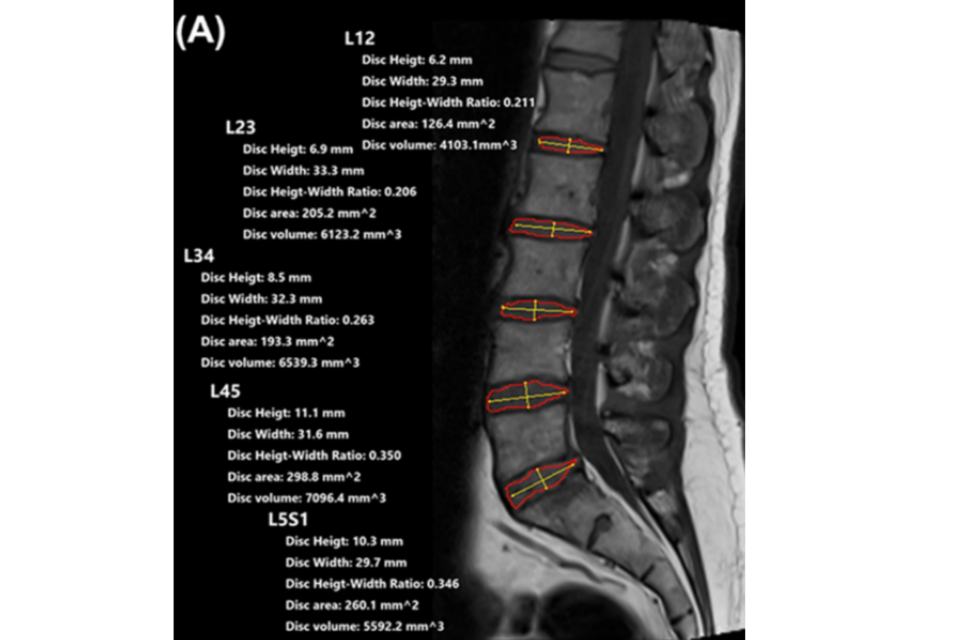

RadiSpine은 MRI, CT, X-ray 등의 영상을 기반으로 환자의 상태에 대한 정량화된 데이터를 제공해 보다 빠르고 정확한 진단과 효율적인 치료 계획을 촉진해주는 영상판독 보조 장치다.

이 같은 AI 기반 시스템은 각종 척추 관련 영상을 의료진에게 선별적으로 제공해 진료 효율성을 높일 것으로 예상된다. 또한 환자에게 정량화된 데이터를 제공해 수술 전·후 환자의 상태를 더 직관적으로 전달할 수 있게 된다.